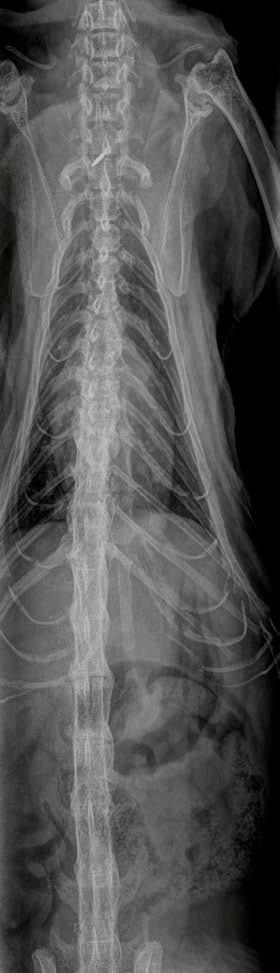

Ultrasonography of the right perineal swelling revealed a fluid-filled object, suspected to be the urinary bladder, herniated through the pelvic diaphragm. Faecal matter was also apparent on ultrasound. Orthogonal survey abdominal radiography was performed. A urethral catheter was placed, and positive contrast cystography performed by instilling 5mL of contrast media (Urografin®; Bayer Australia Ltd, Pymble NSW, 2073, Australia) into the urinary catheter. Repeat orthogonal radiography confirmed urinary bladder retroflexion (Figure 1a). The bladder was then manually reduced into an appropriate anatomical position (Figure 1b). Due to the severity of the deficit, the bladder was unable to remain

Figure 1. Lateral abdominal radiography following positive contrast cystography identifying urinary bladder retroflexion (a). The bladder was then manually reduced into an appropriate anatomical position (b).